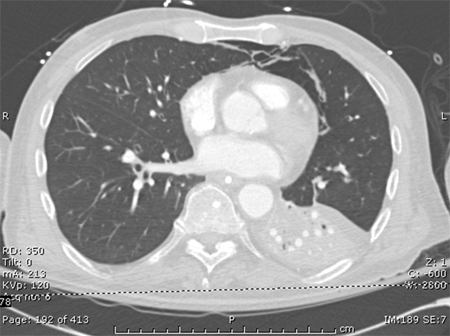

CT scan of a patient with a large, dense left lower lobe infiltrate

Consent obtained at University of Louisville, KY